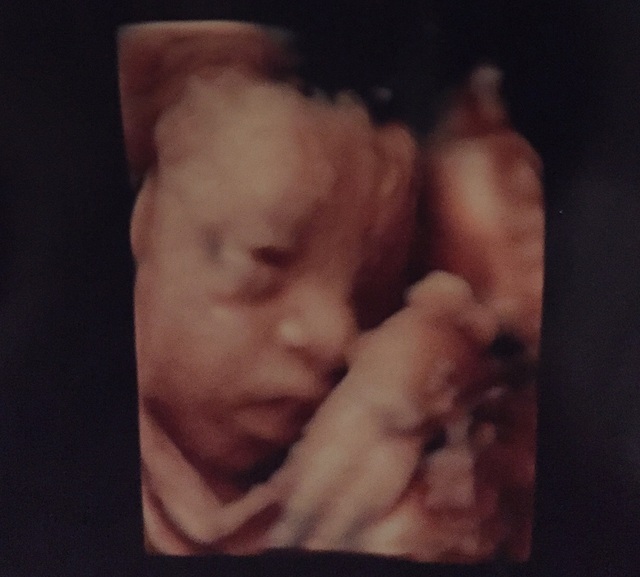

28週0日(28w0d・男の子)|mikamnos さん(34歳)

エコー写真撮影時のエピソード:

横顔の写真なんですが、鼻と口が私に似てると友人に言われてました。まさかこのまま出てくるとも思わなかったのですが、生まれたらこのままの鼻と口でこんなに鮮明に写るモノかとビックリでした。今でも鼻から下は私にそっくりです。